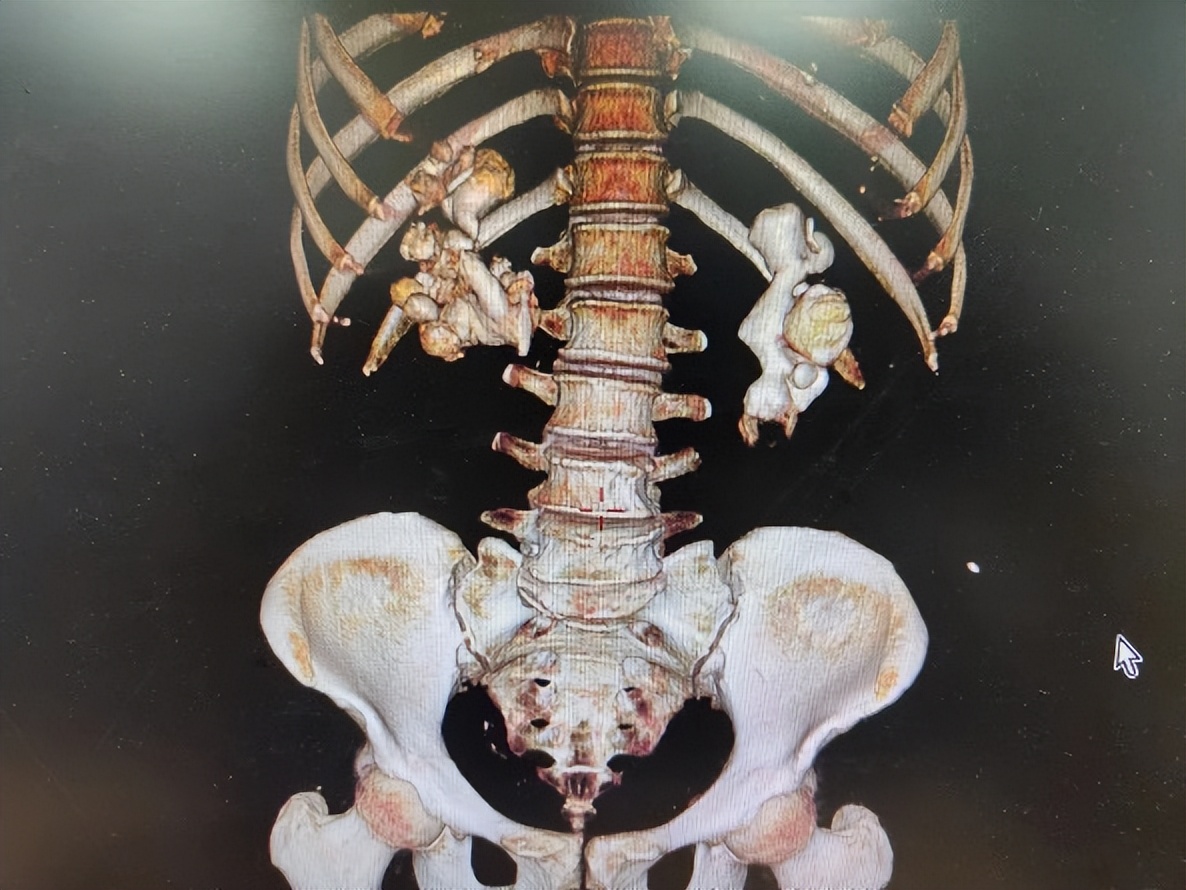

抱着赌一把的心态,患者及家属来找到了黄耀,完善CT等检查后发现,患者双肾柱形结石,两边均超过8cm,每个肾盏都塞满了结石。“我们团队经过讨论后,建议先进行一侧经皮肾镜碎石手术,但是患者结石太大太多,难以取尽,告知患者及家属后,他们虽有诸多疑虑,但还是同意了手术方案。”黄耀回忆道,这个手术采用的多通道模式,最后顺利完成了,将患者大部分结石清除。